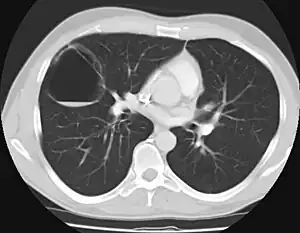

CPAMs are classified into three different types based largely on their gross appearance. Type I has a large (>2 cm) multiloculated cysts. Type II has smaller uniform cysts. Type III is not grossly cystic, referred to as the "adenomatoid" type. Microscopically, the lesions are not true cysts, but communicate with the surrounding parenchyma. Some lesions have an abnormal connection to a blood vessel from an aorta and are referred to as "hybrid lesions."

The earliest point at which a CPAM can be detected is by prenatal ultrasound. The classic description is of an echogenic lung mass that gradually disappears over subsequent ultrasounds. The disappearance is due to the malformation becoming filled with fluid over the course of the gestation, allowing the ultrasound waves to penetrate it more easily and rendering it invisible on sonographic imaging. When a CPAM is rapidly growing, either solid or with a dominant cyst, they have a higher incidence of developing venous outflow obstruction, cardiac failure and ultimately hydrops fetalis. If hydrops is not present, the fetus has a 95% chance of survival. When hydrops is present, risk of fetal demise is much greater without in utero surgery to correct the pathophysiology. The greatest period of growth is during the end of the second trimester, between 20–26 weeks.

A measure of mass volume divided by head circumference, termed cystic adenomatoid malformation volume ratio (CVR) has been developed to predict the risk of hydrops. The lung mass volume is determined using the formula (length × width × anteroposterior diameter ÷ 2), divided by head circumference. With a CVR greater than 1.6 being considered high risk. Fetuses with a CVR less than 1.6 and without a dominant cyst have less than a 3% risk of hydrops. After delivery, if the patient is symptomatic, resection is mandated. If the infant is asymptomatic, the need for resection is a subject of debate, though it is usually recommended. Development of recurrent infections, rhabdomyosarcoma, adenocarcinomas in situ within the lung malformation have been reported.[4]